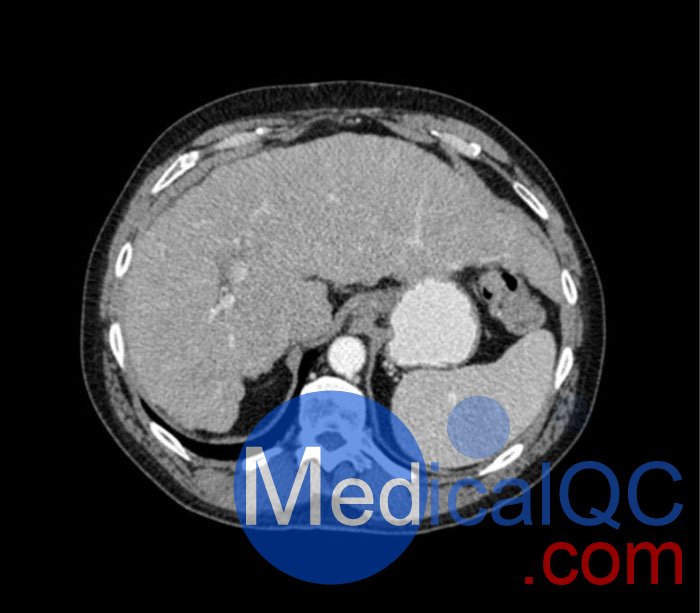

WEK53-04肝硬化腹部模體,WEK53-04門靜脈期腹部模體詳細(xì)介紹:

WEK53-04肝硬化腹部模體,WEK53-04腹部模體模擬了門靜脈期的造影劑增強(qiáng)腹部。它覆蓋了第十胸椎至第三腰椎。

WEK53-04肝硬化腹部模體,WEK53-04腹部模體代表膽囊切除術(shù)后的腹部,帶有小夾子。肝臟有肝硬化的典型體征,在第三腰椎水平植入下腔靜脈過濾器。兩個腎臟都有囊性病變,左側(cè)有一小塊腎結(jié)石。

該模型可用于 CT(包括 CBCT)以評估和優(yōu)化成像性能和后處理應(yīng)用,包括支持 AI 的應(yīng)用。它也適用于培訓(xùn)目的。

該模型提供了對軟組織和骨組織的詳細(xì)而逼真的模擬??障吨刑畛渲s-160HU的纖維素-聚合物復(fù)合材料。

WEK53-04肝硬化腹部模體,WEK53-04門靜脈期腹部模體診斷特征

真實(shí)模擬脈管系統(tǒng)、骨骼和軟組織,包括肝臟、胰腺、脾臟、腎上腺、腎臟、胃、小腸和結(jié)腸。

• 肝硬化

• 膽囊切除術(shù)

• 下腔靜脈濾器

• 腎囊腫

• 腎結(jié)石

• 淋巴結(jié)腫大

WEK53-04肝硬化腹部模體,WEK53-04門靜脈期腹部模體產(chǎn)品成像圖: